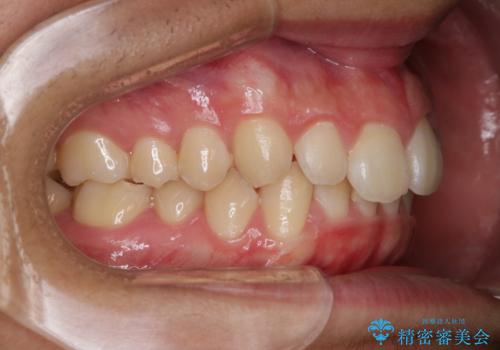

- 上の前歯が見えすぎて気になるとご相談にいらした方です。インビザラインにて前歯の圧下を行うことで歯の見え方の改善し、同時に奥歯の噛み合わせも改善を行いました。

インビザラインを正しく使用して頂けたおかげで、比較的難しいとされる歯の圧下も補助装置を使用せずに行うことが出来ました。上の前歯のラインが整ったことで笑った時の口元の印象を改善させることができ、大変喜んでいただけました。